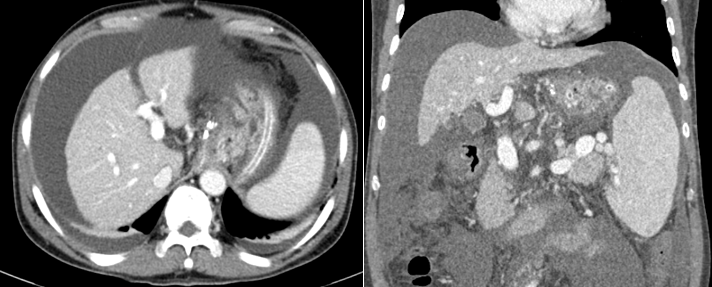

Hình ảnh xơ gan và dịch ổ bụng mức độ nhiều trên phim chụp cắt lớp vi tính của người bệnh